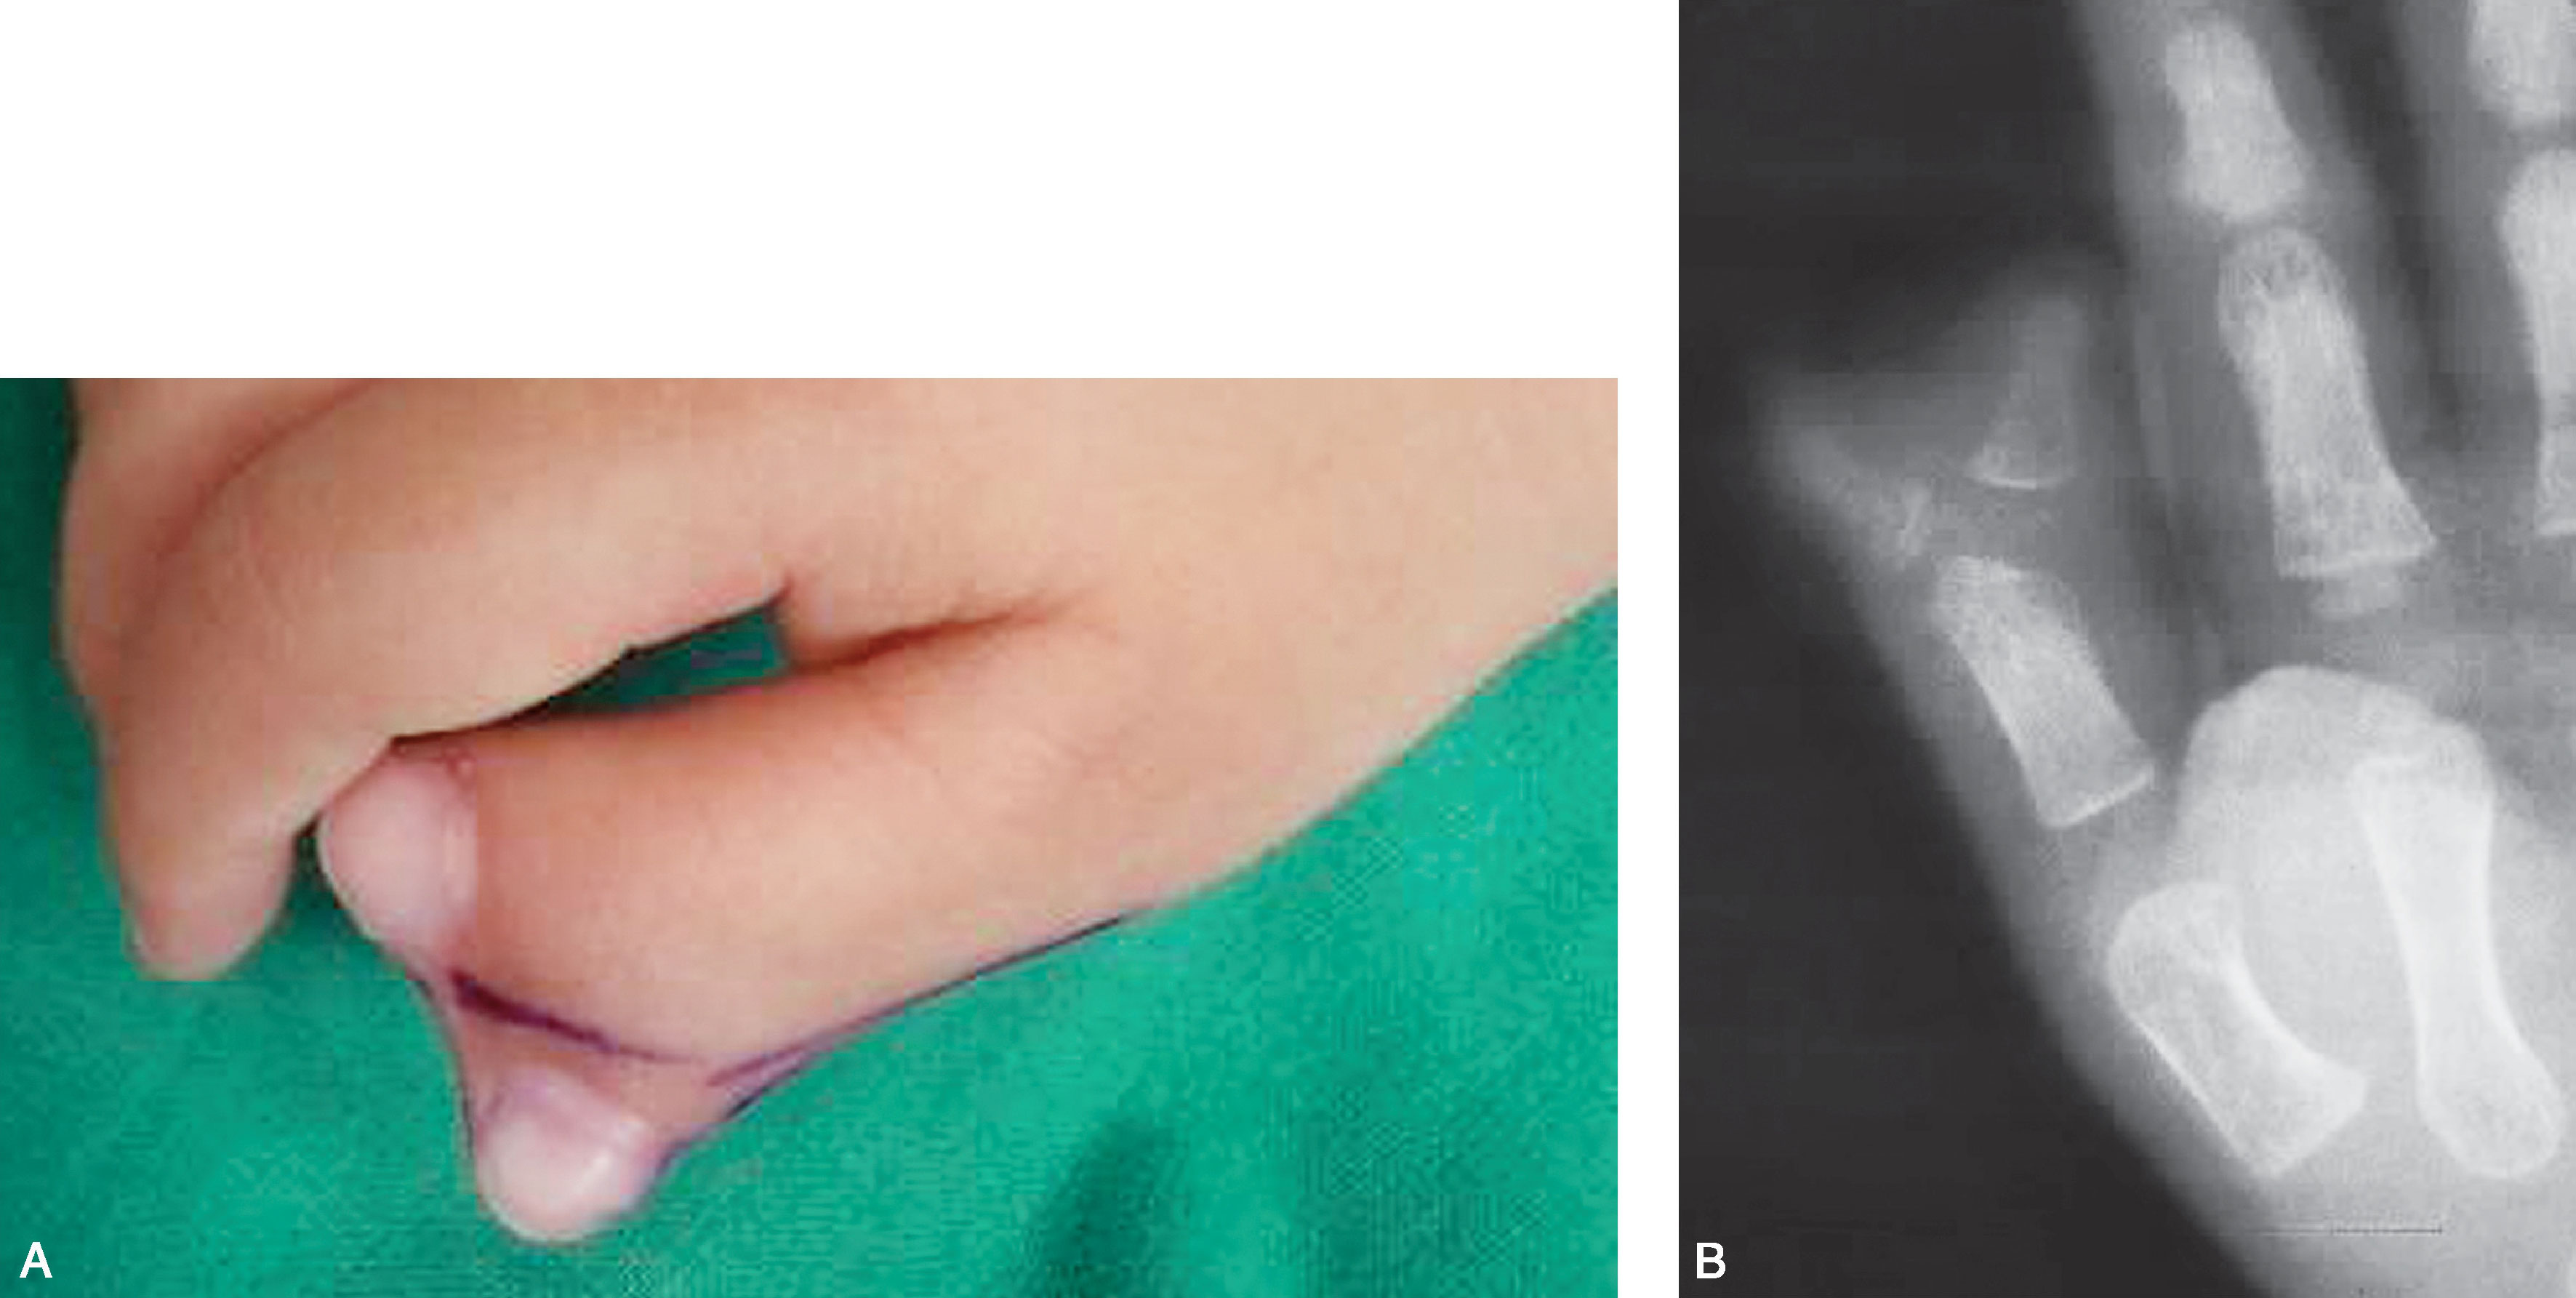

图2-1-65 三拇指畸形病例1

A.右手三拇指畸形,中央拇指发育较好;B.X 线片显示尺侧和桡侧拇指骨关节发育较差,中央拇指骨关节发育相对好,但为三节指骨,选择保留中间拇指,桡、尺侧拇指切除,术中需修复保留的中央拇指掌指关节两侧的关节囊韧带及拇内收肌止点,桡侧需重建拇短展肌止点,近侧指间关节复位固定,远侧指间关节融合